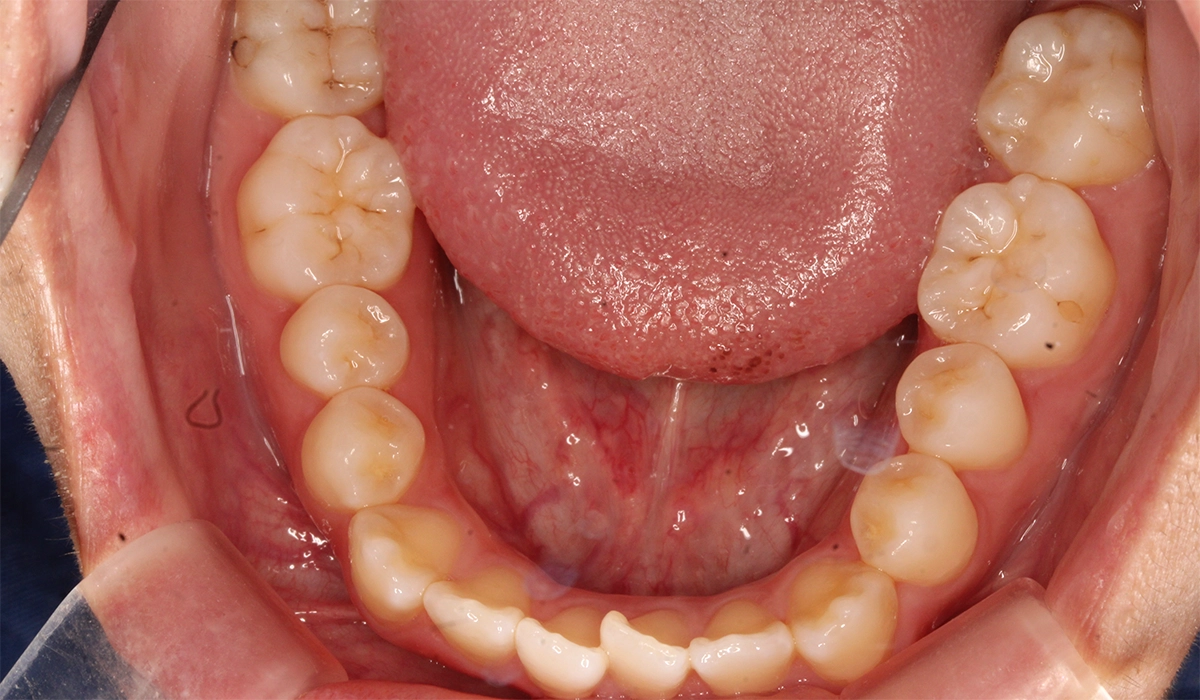

術前:下顎

術後:下顎